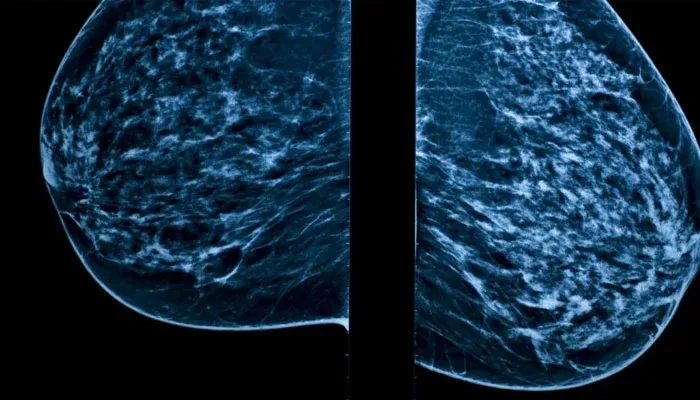

According to findings from The Institute of Cancer Research in London, certain breast cancer cells, when exposed to hormone therapies designed to control cancer growth, can essentially go into a dormant state, similar to hibernation.

The dormant cancer cells can lie dormant for years, only to reawaken later and reignite the cancer. This is how they pose a challenge for treatment. This phenomenon is particularly notable in ER+ breast cancer cases.

It scientists could find a way, it means a glimmer of hope for the thousands of patients battling oestrogen receptor positive (ER+) breast cancer, which accounts for a staggering 80% of all breast cancers.

ER+ breast cancer relies on the hormone estrogen to grow. Doctors typically use various treatments and surgery depending on the patient.